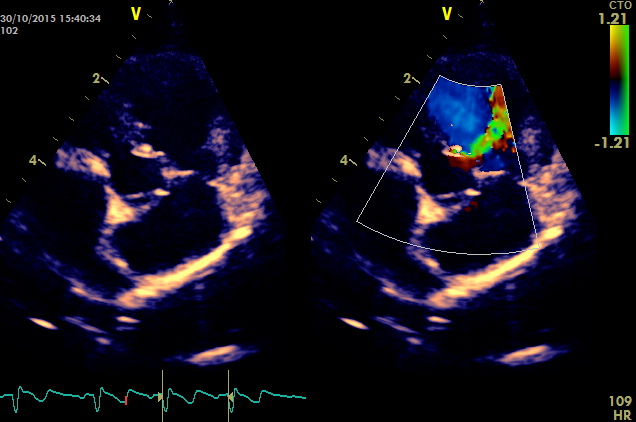

Questo e’ un caso classico che coinvolge la porzione perimembranosa ,la gravita’ del difetto e’ ovviamente proporzionale alla sua ampiezza ,in questo caso il difetto non supera i due millimetri i gradienti tra ventricolo sx e destro sono stimati dal doppler nella norma ,emodinamicamente non dovrebbe comportare lo sviluppo di sovraccarichi significativi del cuore sx . Diversamente i difetti piu’ ampi generano inevitabilmente overcirculation (per lo shunt sx destro emodidamicamente significativo) e sviluppo di scompenso cardiaco sx ,in alcuni casi oltre i due anni l’arteriopatia progressiva generata dall’overcirculation puo’ innalzare la pressione in polmonare e invertire lo shunt.

gradiente transventricolare di 178 mmHg questo e’ un pattern restrittivo compatibile con basse pressioni nel cuore di destra da considerare un bene per il soggetto ,gradienti minori indicano innalzamento delle pressioni nel ventricolo destro .

nessuna evidenza di ingrandimento ventricolare